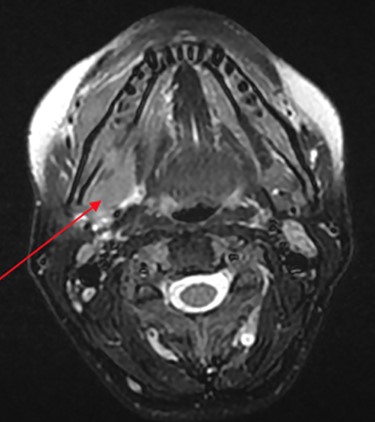

MRI head (axial view) showing Burkitt’s infiltrating the mandible and oral mucosa.